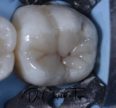

Biomimetic Denture Mimicking Nature in Every Filling

Evening All(e), Had the opportunity to partially replace this old restoration on my chairside’s daughter this afternoon.  I almost forget how much I love this material. #Voco #GrandioSO #FinalTouchTints #Isodam […]